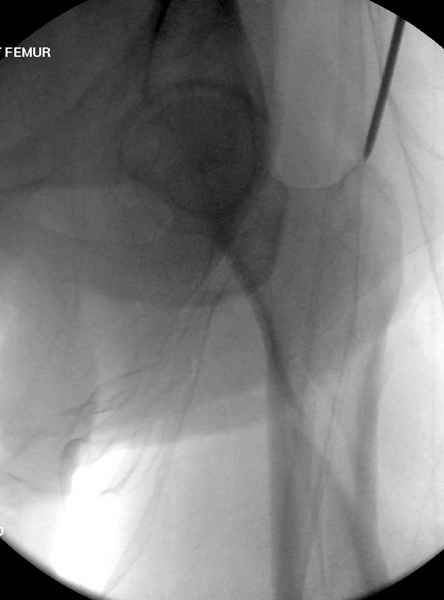

Учитывая, что случай ургентный, больной поступил вечером, не стали делать вытяжение и срочно провели операцию по фиксации перелома бедра антеградным штифтом Versa Nail от DePuy.

Для профилактики дальнейшего раскола в шейке предварительно во время проксимального рассверливания спереди и сзади провели временные спицы, которые в дальнейшем были заменены на шурупы (miss nail method)

Обычная спасательная фасциотомия для обычного больного в этом случае было бы приговором, поэтому несмотря на высокие цифры компартментального мониторинга больного оставили под наблюдением с обкладкой конечности льдом.

Кровотечение удалось контролировать, и больной через пару дней выписан на амбулаторное лечение.